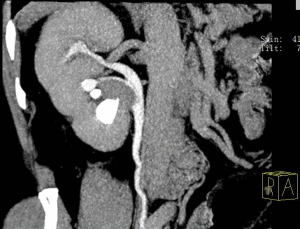

Апаратна діагностика включає в себе рентгенологічне дослідження органів черевної порожнини і зокрема нирок з введенням контрастної речовини, КТ, МРТ, УЗД. Всі ці методи обстеження дозволяють візуалізувати і наочно спостерігати стан нирок і причину затримки у них рідини – перегини або закупорку сечоводів.

Діагноз гідрокалікоз ставиться при надлишку рідини в нирках і збільшення в розмірах чашок і мисок. При цьому симптом затримки сечі повинен бути диференційований з іншими захворюваннями органів черевної порожнини.